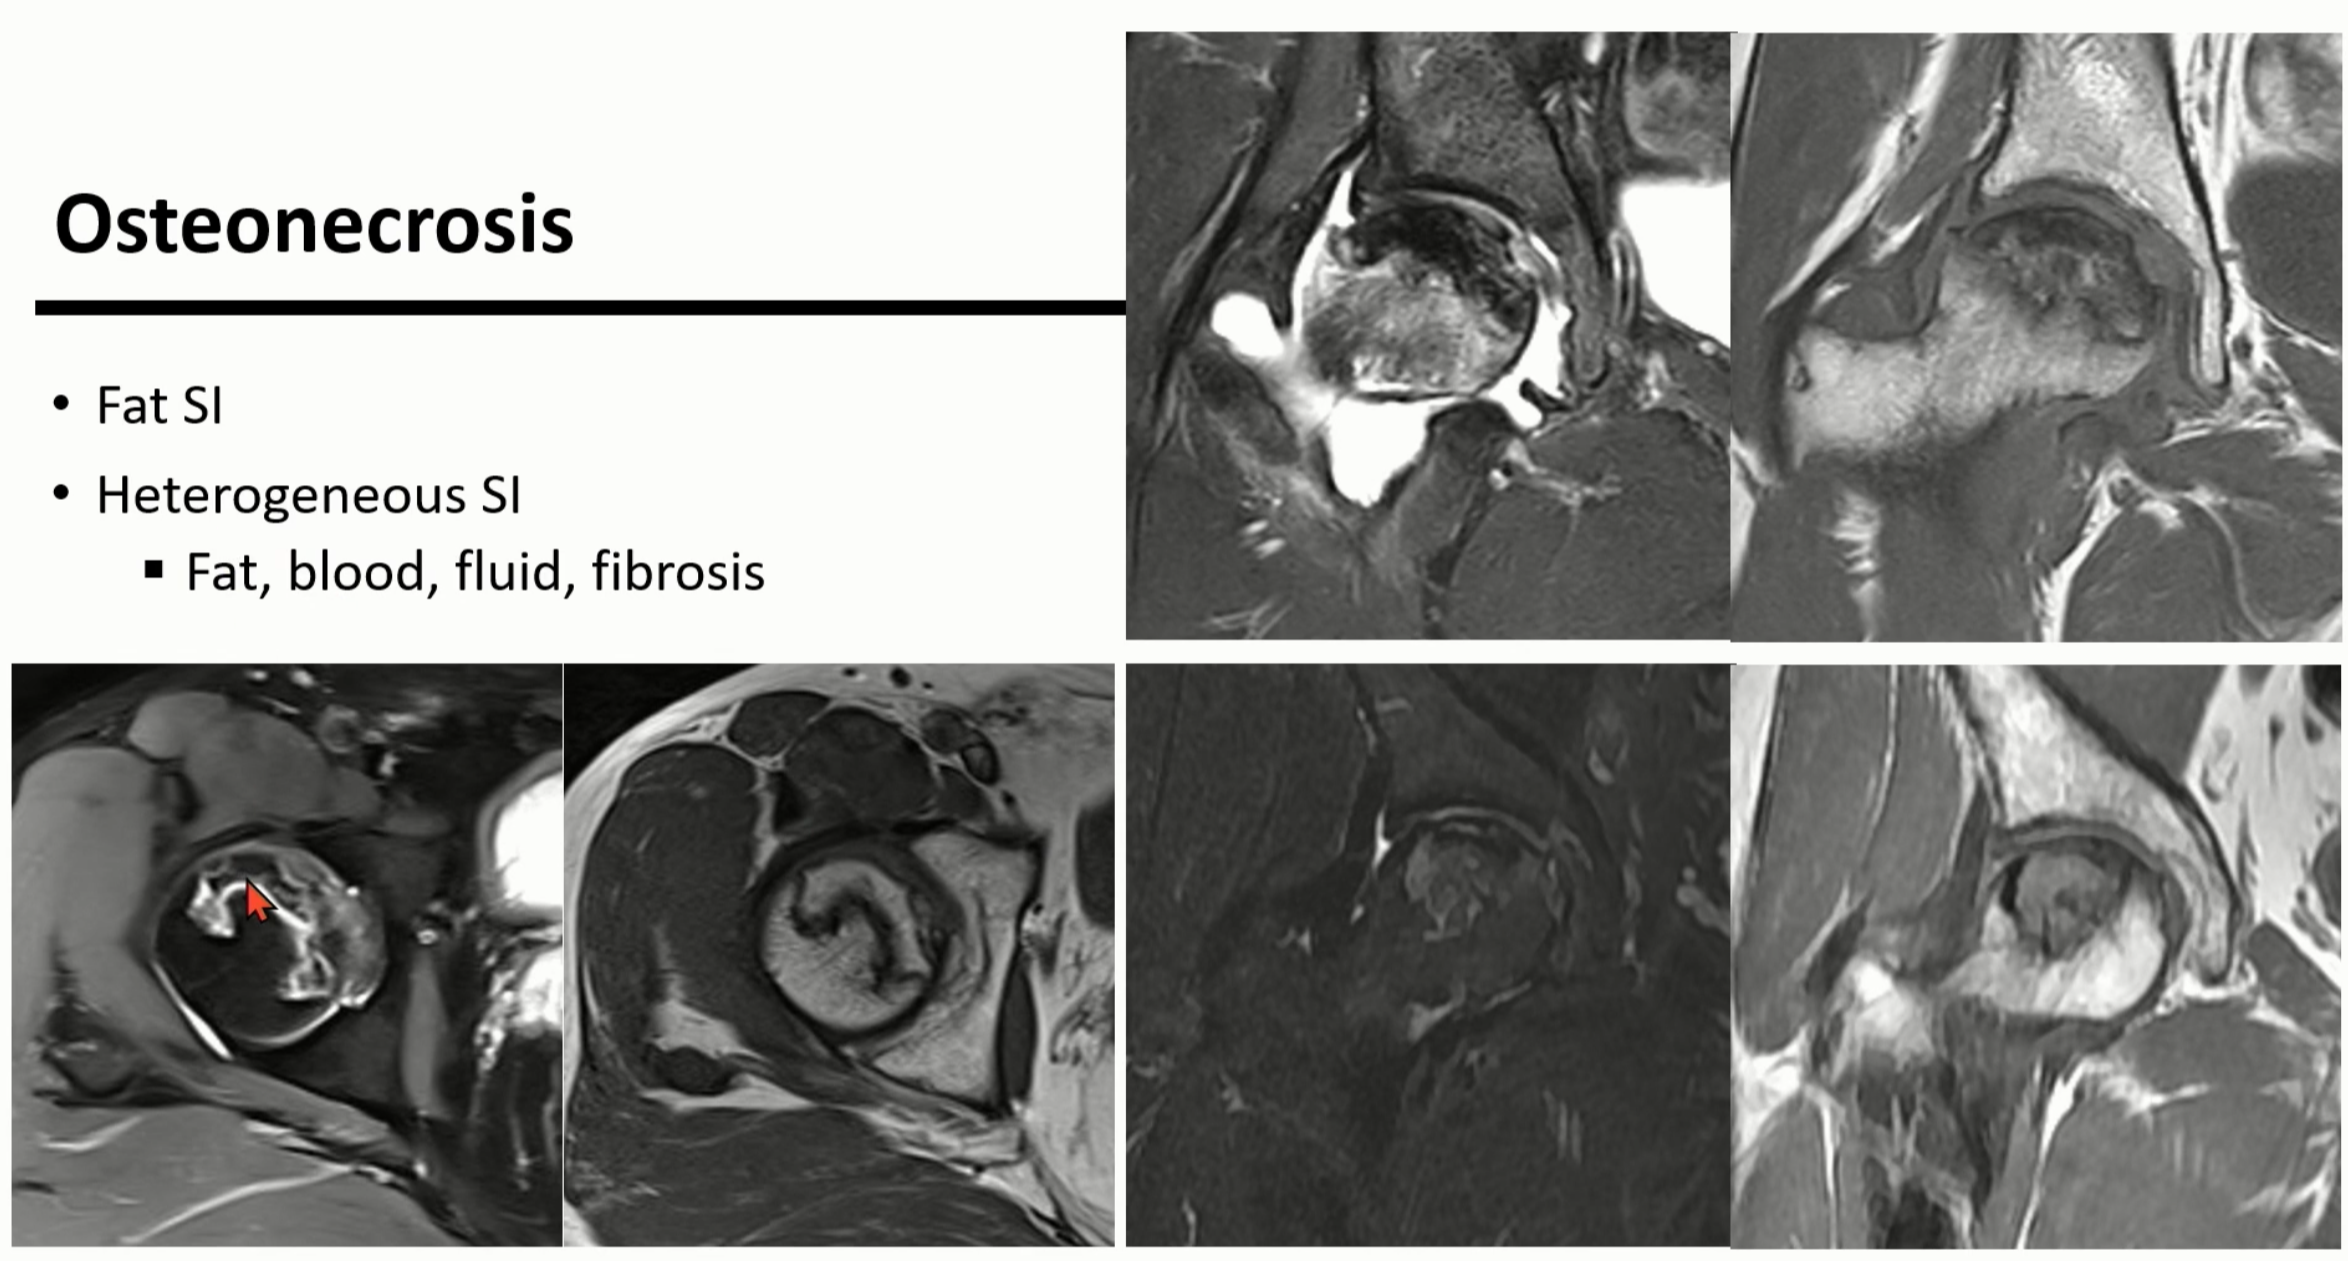

3. 대퇴골두 무혈성괴사

osteonecrosis는 epiphysis와 subchondral bone에서 생기는 bone marrow의 ischemic death입니다.

외상성 혹은 다양한 원인의 비외상성의 원인으로 발생한 혈류의 이상이 지속되면 발생할 수 있습니다.

처음에는 marrow fat necrosis로 관찰되는데, 이는 microscopic change 상태입니다.

(파란색 음영)

이 상태를 복구하기 위해서 Inflammatory fibrovascular infiltration이 노란색 음영 부위에서 진행되게 됩니다.

(주변부로 osteopenia가 진행)

이 단계를 histologic osteonecrosis라고 부릅니다. (비가역 상태)

osteopenic해서 취약해진 부위를 보강하기 위해서 sclerosis가 진행됩니다.(녹색 음영)

sclerosis는 undulating or serpentine한 모양으로 보입니다. (구불구불한 형태)

그 결과, 내부에는 granulation이 있고, 외부에는 sclerosis가 위치합니다.

MRI상 내측의 granulation은 high signal로 보이고, sclerosis는 low signal로 보입니다.

이를 Double-line sign이라고 합니다.

다음 단계로는, 약해져있는 subchondral bone에서 fracture가 관찰됩니다. (붉은 음영)

좌측의 사진에서는 radiolucent line이 관찰됩니다.

(이것을 Crescent sign이라고 부름)

우측 사진처럼 subchondral fracture 부위로 보이는 high Signal을 MR crescent sign이라고 합니다.

더 진행되면 crescent sign이 더 아래로 진행되고, collapse가 일어나면 femoral head의 flattening으로 진행됩니다.

초기에 근위부쪽은 원위부와 동일하게 Fat signal처럼 보이다가, 점점 괴사가 진행되면 지방이 다른 혼합 물질등으로 변화하면서 hetetrogeneous signal로 변하게 됩니다.

femoral head의 flattening으로 진행되면 결과적으로 2차성 골관절염으로 진행되게 됩니다.